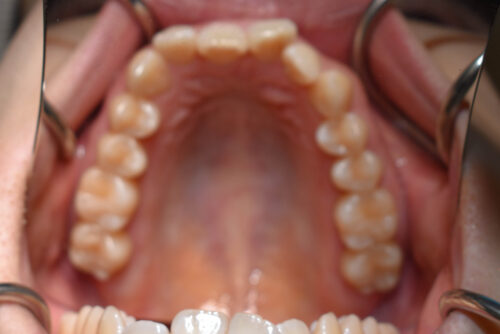

歯のがたつき(叢生)と過蓋咬合を非抜歯矯正治療で治した症例(かみ合わせ変化10か月)

初診時年齢 27歳 女性

歯のでこぼこ(叢生)

と

過蓋咬合

を主訴に

右側が アングル2級とよばれる

出っ歯傾向の状態で

上の正中が

半歯分 ずれている状態でした。

また 下あごの 歯が見えず

過蓋咬合を呈していました。

ワイヤー矯正治療10か月後です。

本症例も

上顎左右臼歯部に

歯科矯正用アンカースクリュー(デュアル・トップオートスクリュー)を用い

下あごを オートローテーションさせ

また 上下の歯列全体を

後方へ移動させることで

歯を抜かなくても

口元の改善も行いました。

上下の正中には 若干ずれが残存しましたが、

かみ合わせ重視で

終了いたしました。